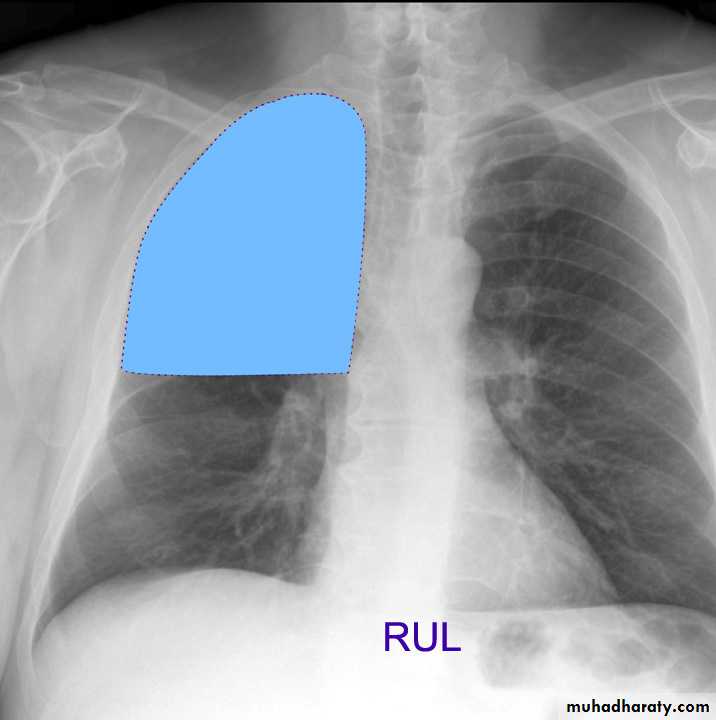

Lung Anatomy

Zonal anatomyLobar anatomy

Rt lung divided to 3 lobes (upper , middle & lower )

Transverse fissure separate the upper lobe from middle lobeOblique fissure separates the upper & middle from lower lobe .

Rt upper lobe